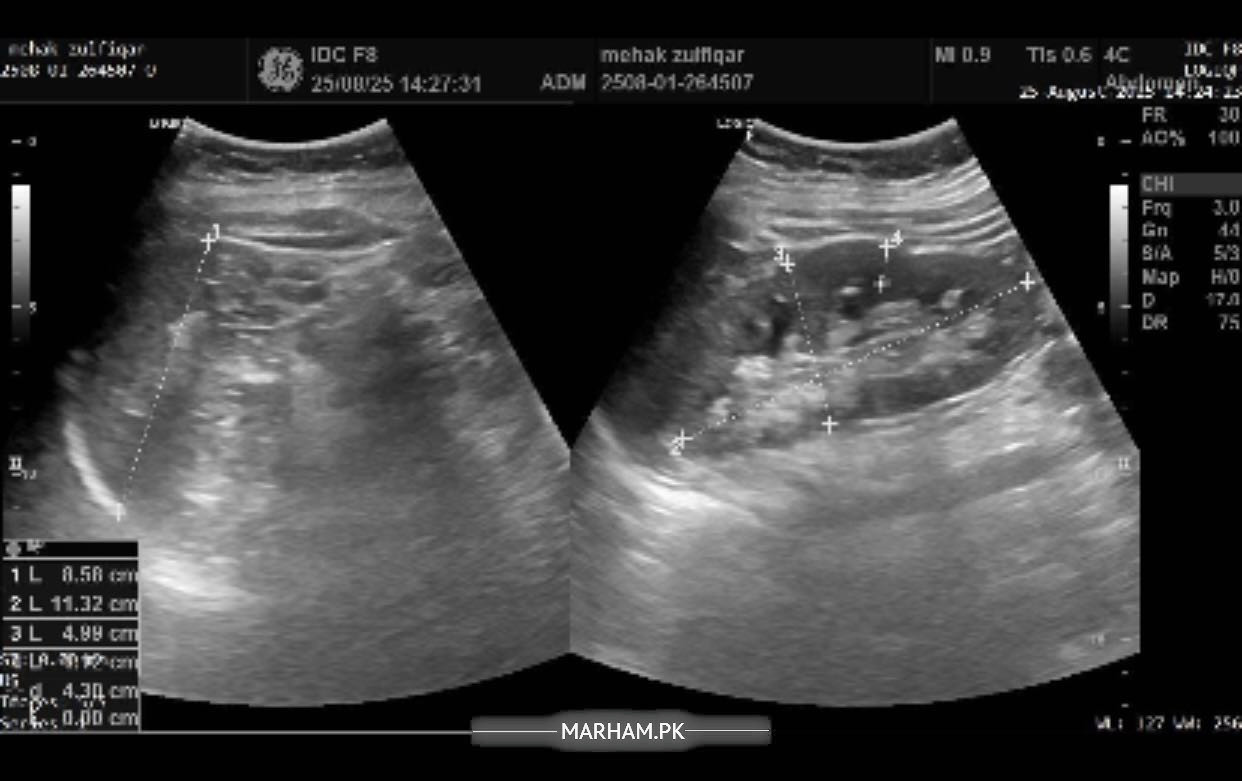

Pain in the right side of abdomen under the ribs followed by backache in the same area. In addition to these symptoms having difficulty concentrating, having confusion, difficulty speaking facial muscles hurt, sleepiness all the time, fluctuations in bp and feel nauseous with sometimes developed fever or shivering. Please help me with this. Will be highly thankful. Attached my reports too.

Sr this is the most recent ultrasound report. But radiology isn’t matching my blood reports. I am worried about that. Pls help.

Sr can’t share pics altogether but here it is

Another

report of ultrasound

you’re demonstrating features of UTI, blood in urine can be due to many things, would like to explore this in detail and get to do few more tests. I’m available for consultation

Okay I think you need proper consultation, and a proper ultrasound from a consultant. I’m available or if you want to see anybody of your liking you should. in the meantime i need you to make a record of your bp for a week, 2 readings in the morning and 2 readings at night then tell me